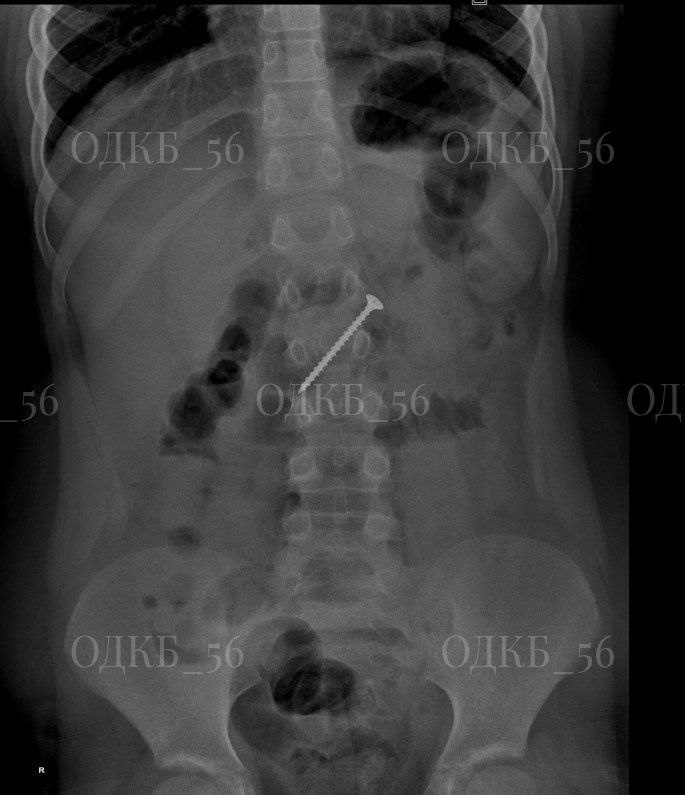

В Оренбурге из кишечника ребёнка достали саморез

В Оренбургской областной детской клинической больнице провели успешную операцию по извлечению крупного инородного тела у 9-летнего пациента. Как сообщили в медучреждении, ребенок поступил в приемное отделение по направлению из районной больницы с подозрением на проглатывание самореза. Обследование подтвердило опасения родителей: рентгенография показала наличие инородного тела в области желудка. В экстренном порядке команда специалистов провела эндоскопию верхних отделов ЖКТ под общим обезболиванием. Во время операции выяснилось, что саморез длиной около 5 см мигрировал в двенадцатиперстную кишку, что создавало прямую угрозу жизни ребенка. Был риск развития кишечной непроходимости или перфорации стенки кишки. Врачам удалось извлечь опасный предмет. В настоящее время маленький пациент был выписан домой в удовлетворительном состоянии. В лечебном учреждении отметили, что подобные случаи носят массовый характер. Регулярно в бошльницу поступают дети с инородными телами в пищеводе и дыхательн

Обследование подтвердило опасения родителей: рентгенография показала наличие инородного тела в области желудка. В экстренном порядке команда специалистов провела эндоскопию верхних отделов ЖКТ под общим обезболиванием.

Во время операции выяснилось, что саморез длиной около 5 см мигрировал в двенадцатиперстную кишку, что создавало прямую угрозу жизни ребенка. Был риск развития кишечной непроходимости или перфорации стенки кишки. Врачам удалось извлечь опасный предмет. В настоящее время маленький пациент был выписан домой в удовлетворительном состоянии.